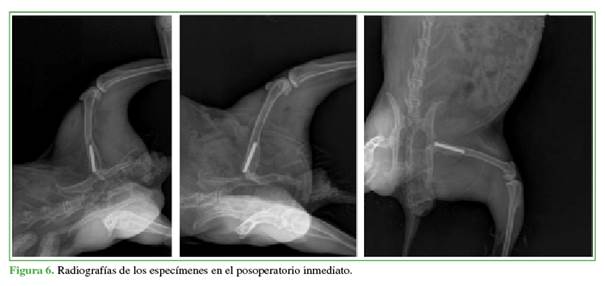

Se evaluaron con radiografías a los especímenes desde el posoperatorio inmediato hasta las 12 semanas después de la implantación para verificar la colocación adecuada del implante y descartar fracturas, y nuevamente en la extracción para documentar la incorporación del implante sin incidentes (Figura 6). Luego los conejos fueron sacrificados y se obtuvieron los fémures de todos los animales. Se tomaron radiografías de estos fémures en proyecciones de frente y de perfil, para el análisis mediante la división de Gruen y lograr puntualizar las zonas de crecimiento óseo (Figura 7).